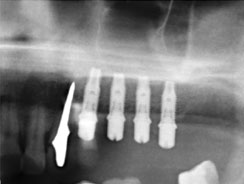

Имплантация

Одноэтапная имплантация

Синус-лифтинг